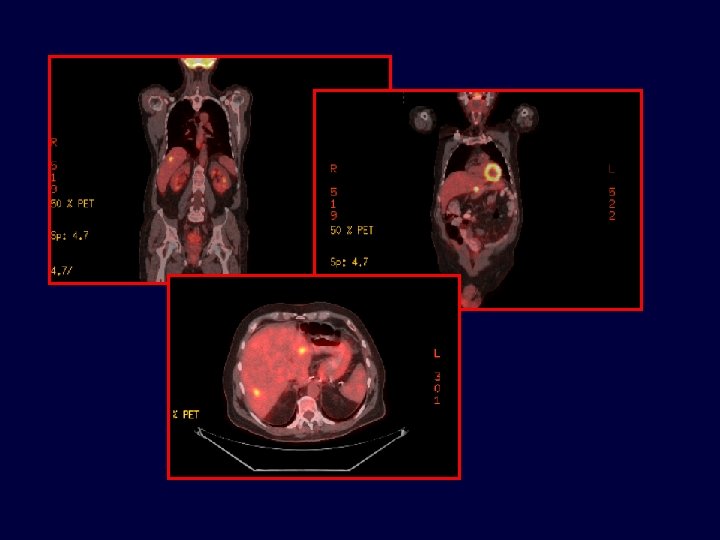

• Caso clínico • Paciente de 71 años con cáncer de colon estadío III en 07/2004, Metástasis hepáticas en 06/2008 • 65 años, enfermedad coronariana, médico. Resección carcinoma de colon T 3 N 1 M 0 • 07/2004 • Termina FOLFOX x 12 03/2005 06/2008 11/2008 06/2010 • - Lesiones hepáticas – ambos lóbulos

Caso clínico Paciente de 71 años con cáncer de colon estadío III en 07/2004, metastasectomía hepática en 11/2008 65 años, enfermedad coronariana, médico. Resección carcinoma de colon T 3 N 1 M 0 07/2004 Termina FOLFOX x 12 Metastasectomía hepática luego de FOLFIRI + Bevacizumab x 3 meses 03/2005 06/2008 11/2008 06/2010 - Lesiones hepáticas Quimioterapia postoperatoria con FOLFIRI + Bevacizumab - K-ras nativo

• 16/06/2010